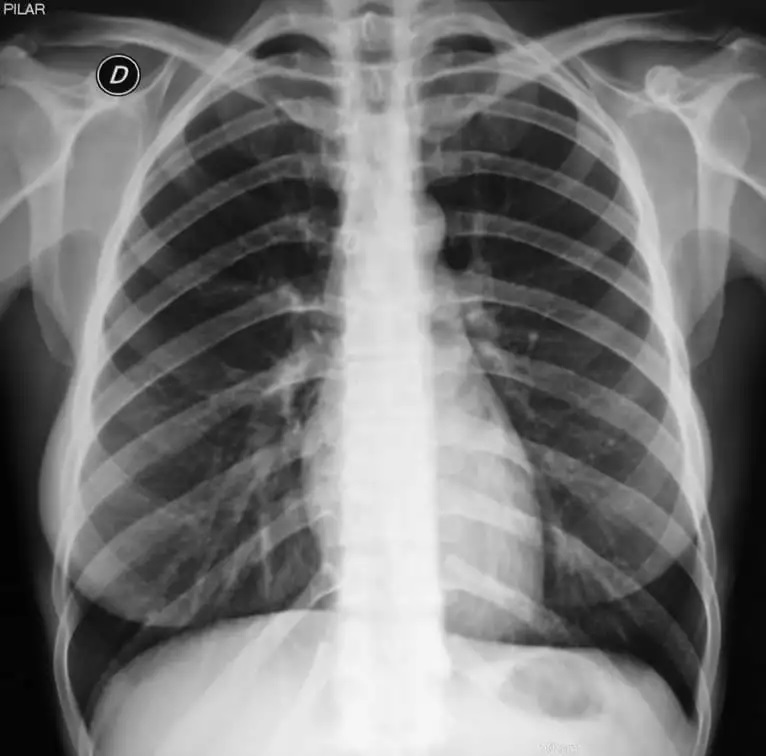

O exame de Raio X Tórax PA OIT (Projeção Posteroanterior de Tórax conforme a Organização Internacional do Trabalho) é um procedimento essencial para a avaliação de doenças pulmonares, especialmente aquelas relacionadas à exposição ocupacional a poeiras minerais, como a silicose, asbestose e outras pneumoconioses. Este exame radiológico segue os padrões estabelecidos pela OIT, garantindo uma análise detalhada e padronizada das condições pulmonares dos trabalhadores.

Para empresas que operam em setores como mineração, construção civil, e indústrias que envolvem exposição a poeiras e agentes químicos, o RX Tórax PA OIT é uma ferramenta indispensável para o monitoramento da saúde respiratória dos colaboradores. Realizar esse exame regularmente é uma medida preventiva crucial para detectar precocemente doenças pulmonares ocupacionais, permitindo que a empresa tome as ações necessárias para proteger seus trabalhadores e cumprir com as normas de saúde e segurança.